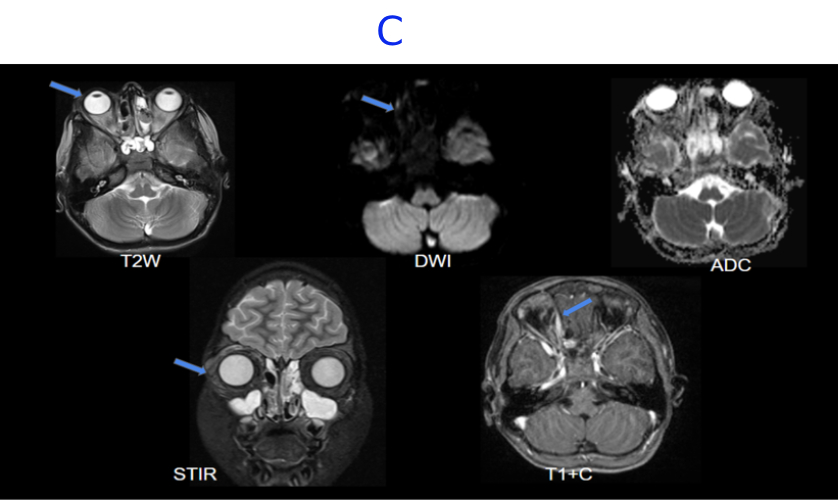

C. MRI BRAIN WITH IV CONTRAST - DAY 11- STATUS POST DECOMPRESSION

C. Near complete resolution of the right globe proptosis.Interval reduction in the thin enhancing collection along the medial wall of right orbit demonstrating minimal diffusion restriction.Near complete resolution of the extensive T2/STIR hyperintense edema noted in right periorbital soft tissue and orbital compartments with minimal residual edema in the preseptal space.Near complete resolution of the soft tissue stranding involving postseptal fat, surrounding the extraocular muscles.